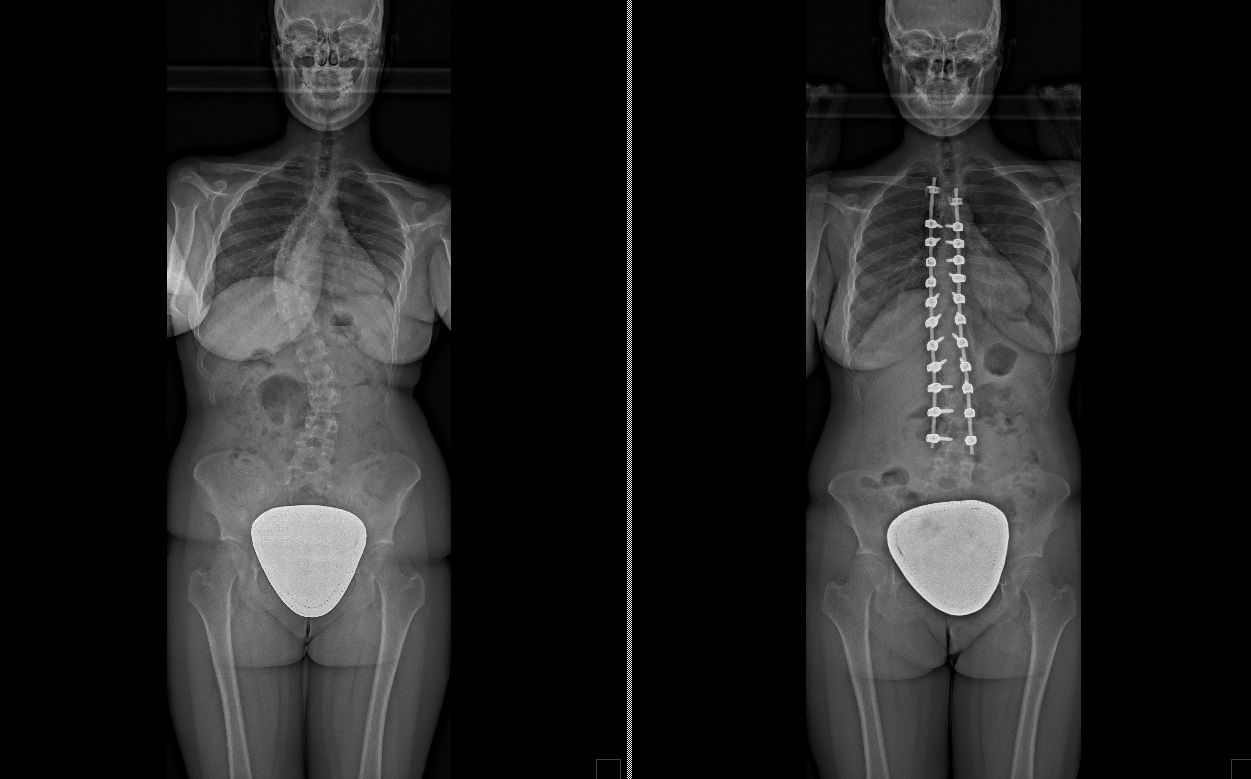

Foto e video